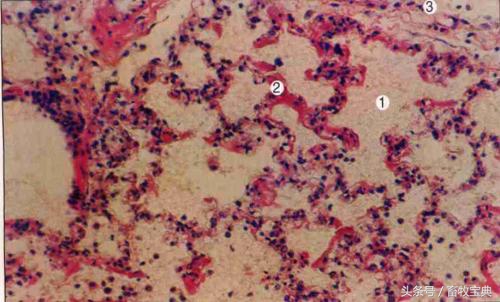

肺炎型主要表现为纤维素性肺炎和浆液纤维素性胸膜炎。肺组织颜色从暗红、炭红到灰白,切面呈大理石样景象。随病变发展,在肝变区内可见到干燥、坚实、易碎的灰黄色坏死灶,个别坏死灶周围还可见到结缔组织形成的包囊。胸腔积聚大量有絮状纤维素的浆液。此外,还常伴有纤维素性心包炎和腹膜炎。